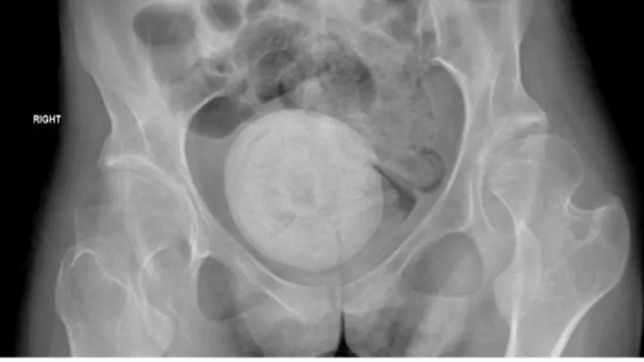

A paciente tem paralisia cerebral e foi levada ao hospital por seus pais. Além das dores abdominais, ela também teve febre, calafrios, vômitos e diminuição do apetite. Os exames de imagem mostraram uma estrutura redonda calcificada na pelve ocupando espaço entre a bexiga e o reto, provavelmente empurrando para cima o útero ocupando o espaço vaginal, medindo 9 × 10 cm.

Uma mulher libanesa de 27 anos foi levada às pressas para o hospital após sentir fortes dores abdominais por três dias. Chegando ao pronto-socorro, ela foi submetida a uma radiografia e uma tomografia computadorizada que apontaram haver uma grande pedra dentro de sua cavidade vaginal. O caso foi descrito na revista científica Urology Case Reports por cientistas do departamento de urologia do Hospital AL-Zahraa, de Beirute, e da Lebanese University.